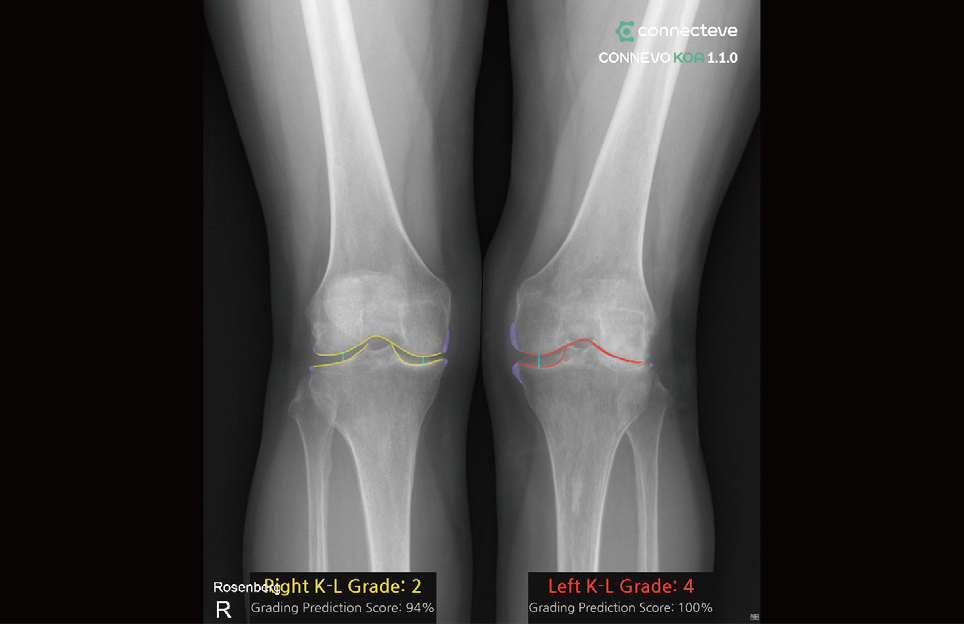

By combining more than 100,000 high-quality proprietary medical data cases with deep learning technology, CONNECTEVE has introduced CONNEVO KOA, CONNEVO Metric, and CONNEVO Suite. Recently, the company obtained European CE MDR certification and conducted PoC projects in the Middle East, demonstrating its technological capabilities in the global market and continuing its growth trajectory.

CONNECTEVE’s CONNEVO Metric automatically measures lower-limb alignment and angular data, enabling data-based comparison of pre- and post-surgical changes. CONNEVO Suite integrates these diagnostic data and provides an environment optimized for clinical workflow, improving hospital operational efficiency. A key strength is its ability to reduce variability that may arise from manual measurement processes, and enable explanations based on objective numerical values.